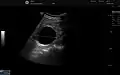

Simple renal cyst.jpg

Simple renal cyst

A renal cyst is a fluid collection in or on the kidney. There are several types based on the Bosniak classification. The majority are benign, simple cysts that can be monitored and not intervened upon. However, some are cancerous or are suspicious for cancer and are commonly removed in a surgical procedure called nephrectomy.